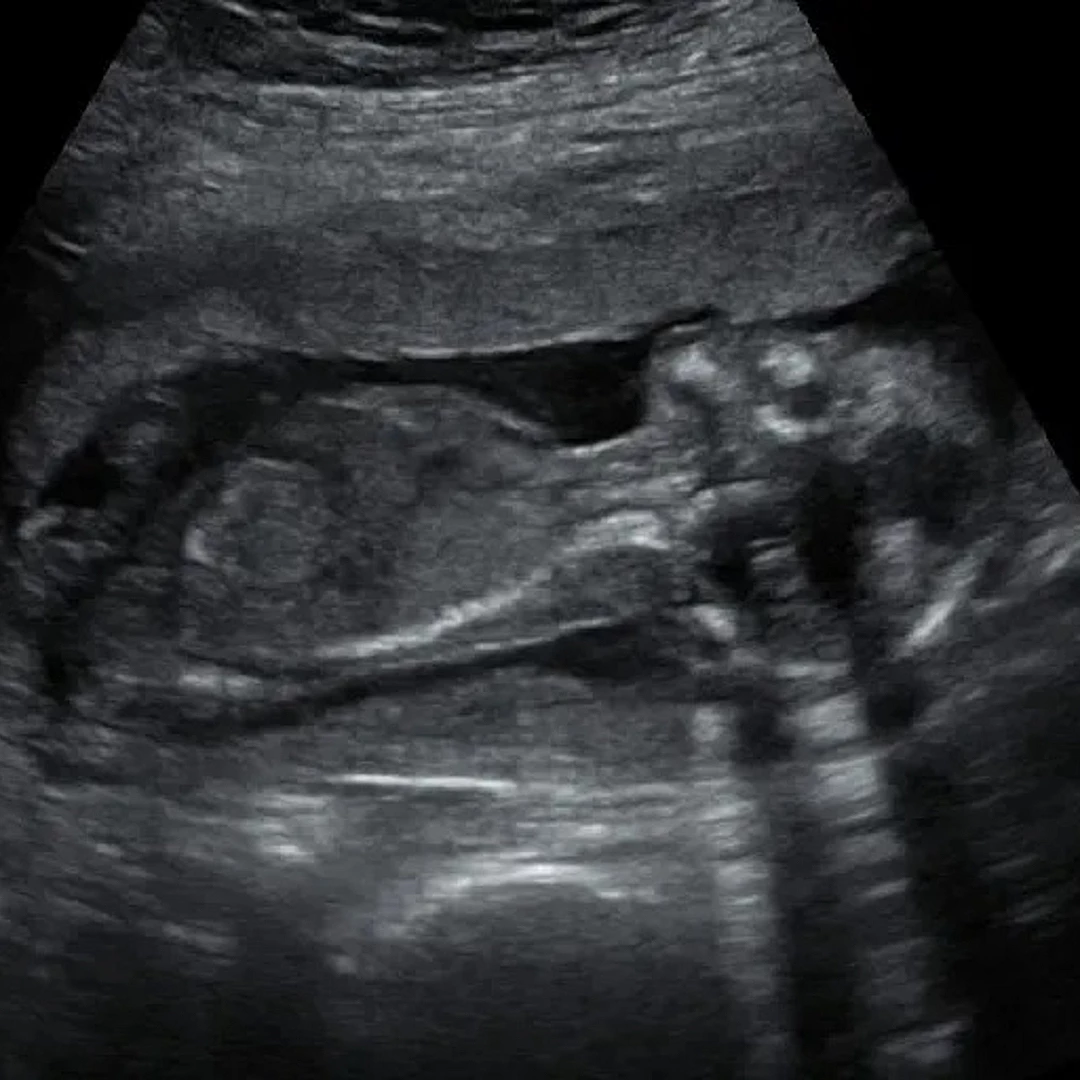

Obstetrics Ultrasound

Obstetrics Ultrasound monitors the health and development of the fetus during pregnancy using safe, real-time imaging. It helps assess fetal growth, detect anomalies, and guide prenatal care.